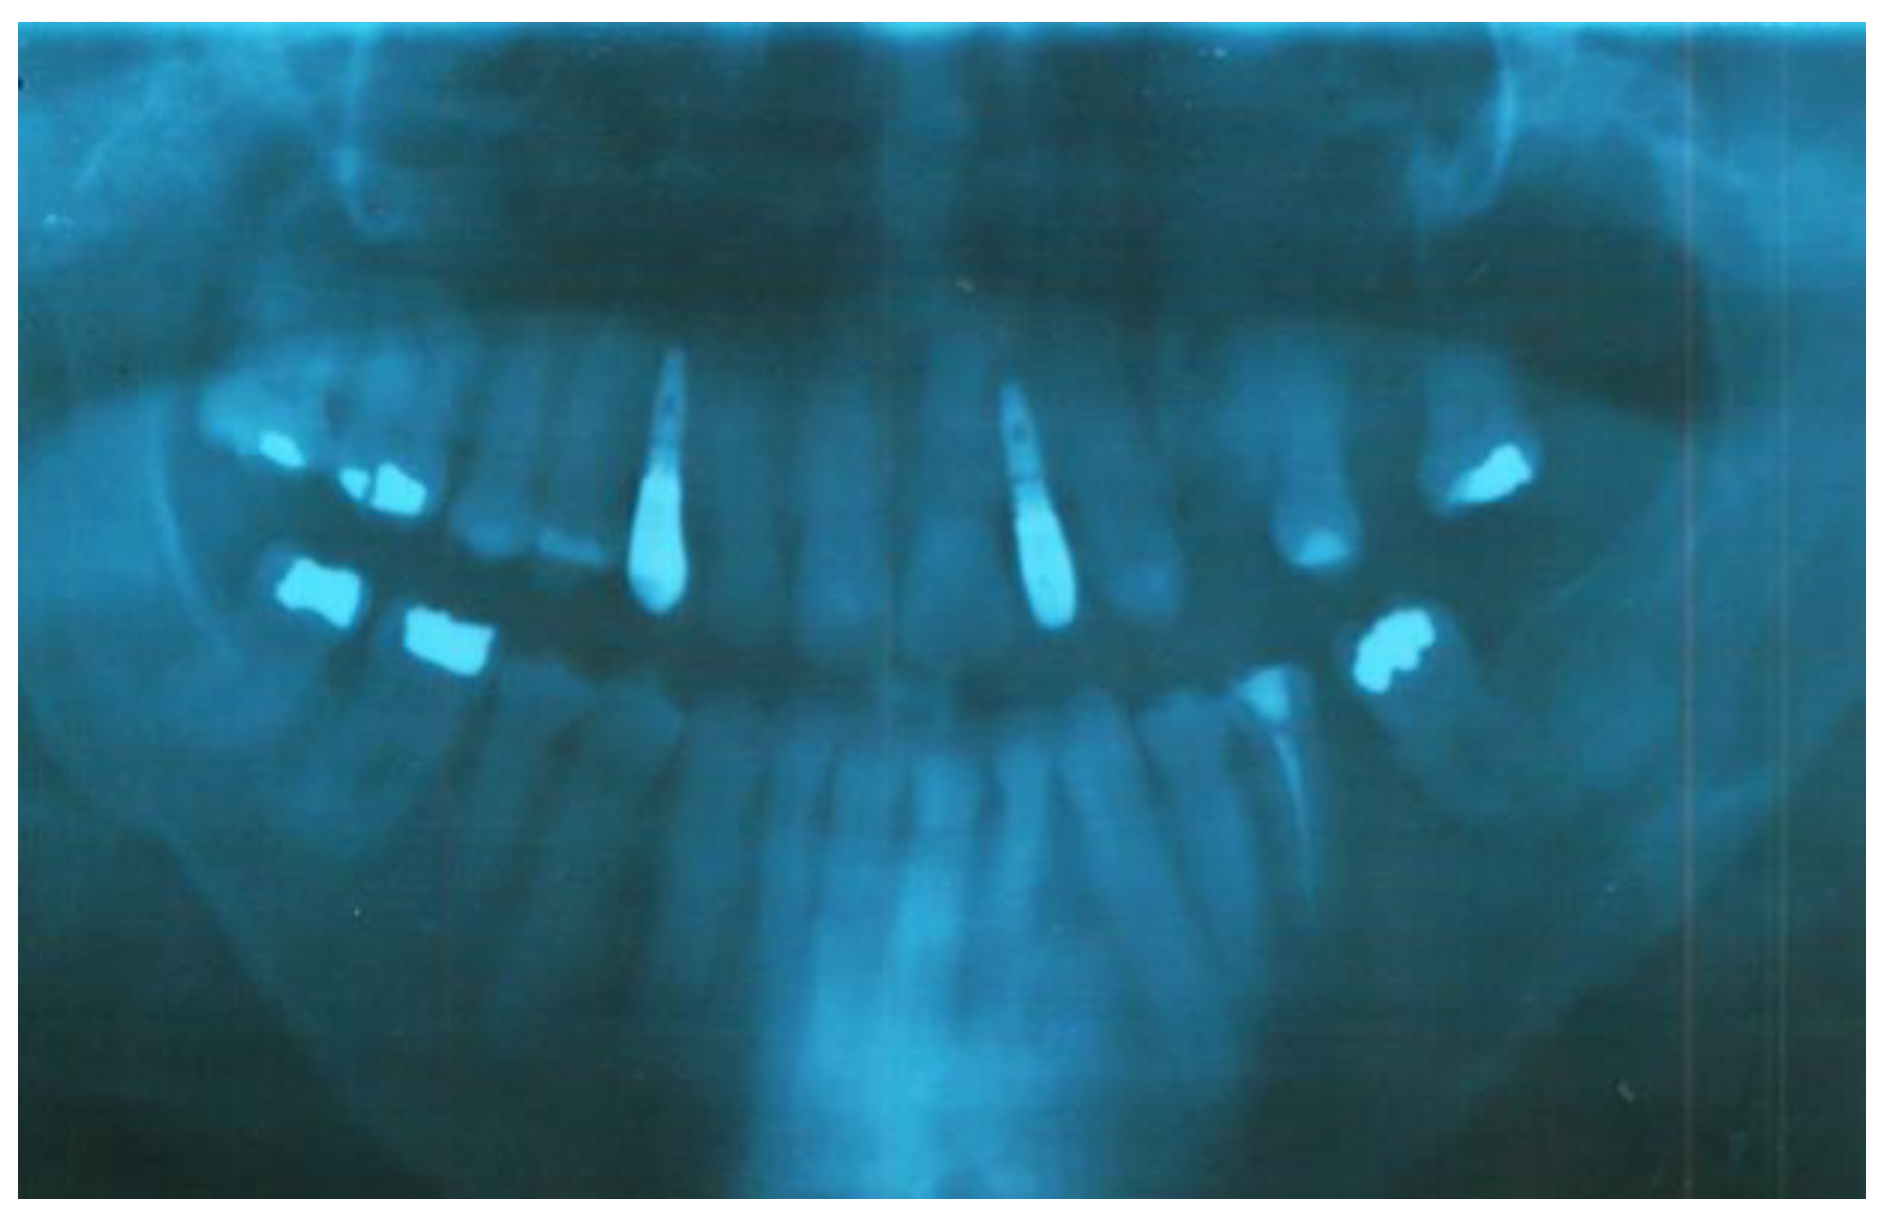

Clinical oral examination revealed dentition with numerous missing teeth (Table 1 and Figure 2), and the panoramic radiograph showed radiculomegaly in the upper right central incisor, upper left canine, first lower left premolar, lower right and left canine, lower right central incisor, lower left central incisor, lower right lateral incisor, and first lower right and left premolar.

The first upper left molar, upper right canine, upper left lateral incisor, first upper left premolar, first upper right molar, first lower right molar, and first lower left molar are absent (Figure 3).

Figure 3. Pre-treatment panoramic radiograph of patient showing several missing teeth, radiculomegaly, and dilaceration of roots.